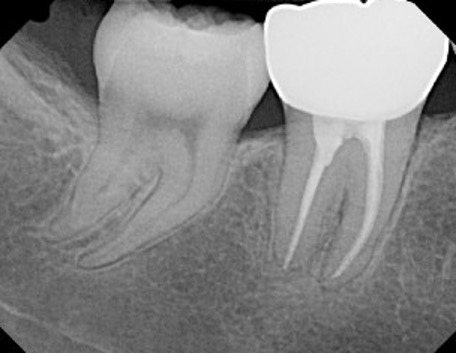

● Before beginning the treatment, the dentist takes an x-ray of the tooth to assess the tooth decay and severity of infection. Moreover, the number of the tooth roots and their curvature are also checked. In curved and calcified roots some endodontist advice CBCT to check the diameter and anatomy of roots in details.